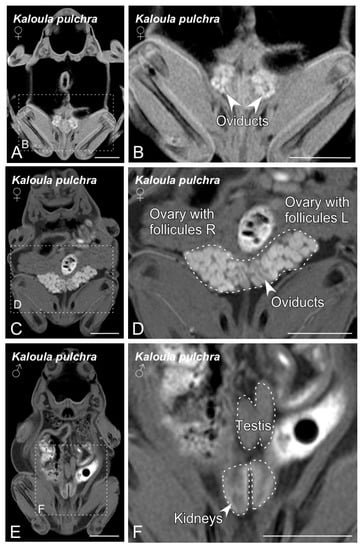

3.1. BT-MRI

3.2. Ultrasonography